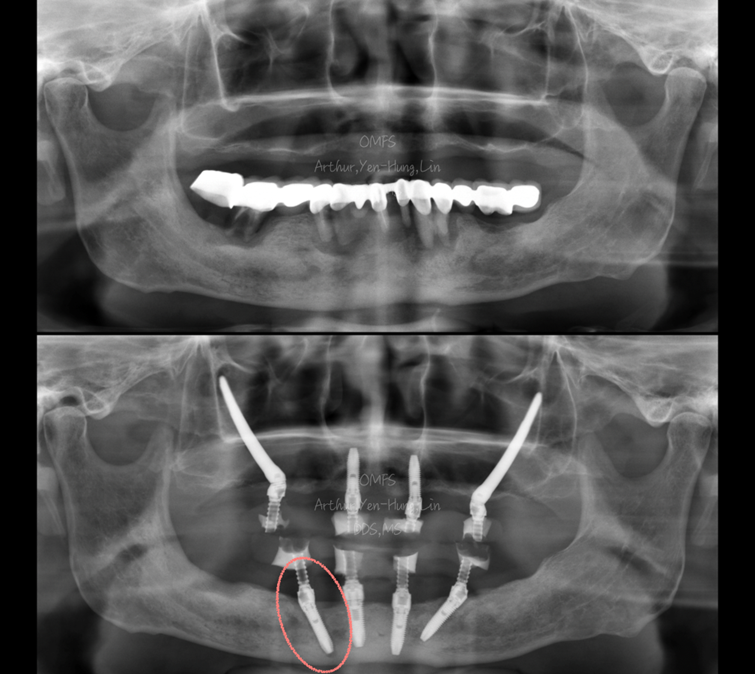

患者為 67 歲男性,有高血壓與糖尿病病史,口內檢查發現上顎缺牙下與顎嚴重牙周病,完成上下顎全口重建後約 3 個月,回診發現右下後牙區 #45植體骨整合失敗。

考量患者已進入全口重建流程,且希望降低再次手術的侵入性,我們採取「單顆植體救援重新植入」策略:

1. 利用下顎前牙區兩支已骨整合成功的植體作為固定基座。

2. 製作可用螺絲鎖附的客製化 X-Clip,提供導航手術穩定參考。

3. 以此完成 #45 植體重新植入,不需再打骨釘固定、切口更小,同時能維持既有臨時假牙的設計。